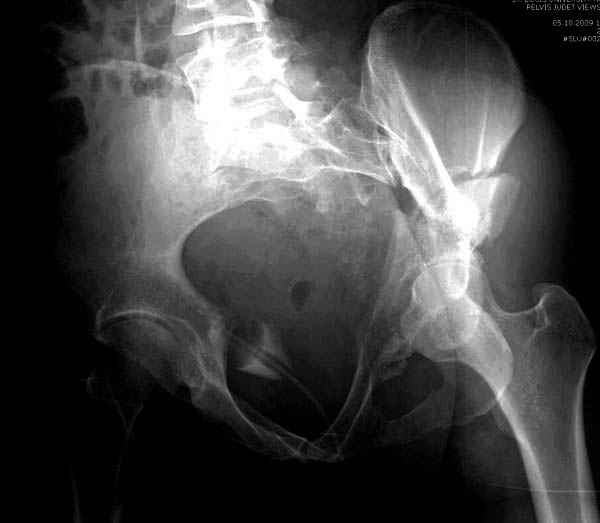

Все выступающие коллеги высказались насчет необходимости стандартных снимков по Judet, потому что для определения тактики лечения переломов вертлужной впадины 3Д снимки малоинформативны.

Летурнель разработал классификсацию на основании прямого, запирательного и подвздошного рентген снимков, котоые, кроме описания характера переломов, также подсказывают адекватный доступ для репозиции перелома.

Из того минимума, что представлено, мне кажется, мы имеем дело с двухколонным переломом вертлужной впадины. Обычно медиальный (центральный) "вывих" головки встречаются в сложных двухколонных переломах со смещением.

По-моему, надо готовить больного к будущей артропластике, но без опоры на задний столб невозможно удержать протез. Опорная конструкция (кольца и т.д.) должны иметь опору, и поэтому мы бы сделали реостеосинтез задним доступом. При надобности остеотомия и рутинная фиксация с межколонными винтами.

Здесь несколько вариантов двухколонных свежих переломов, которые были оперированы из одного-заднего, а также из двух: переднего и заднего доступов.